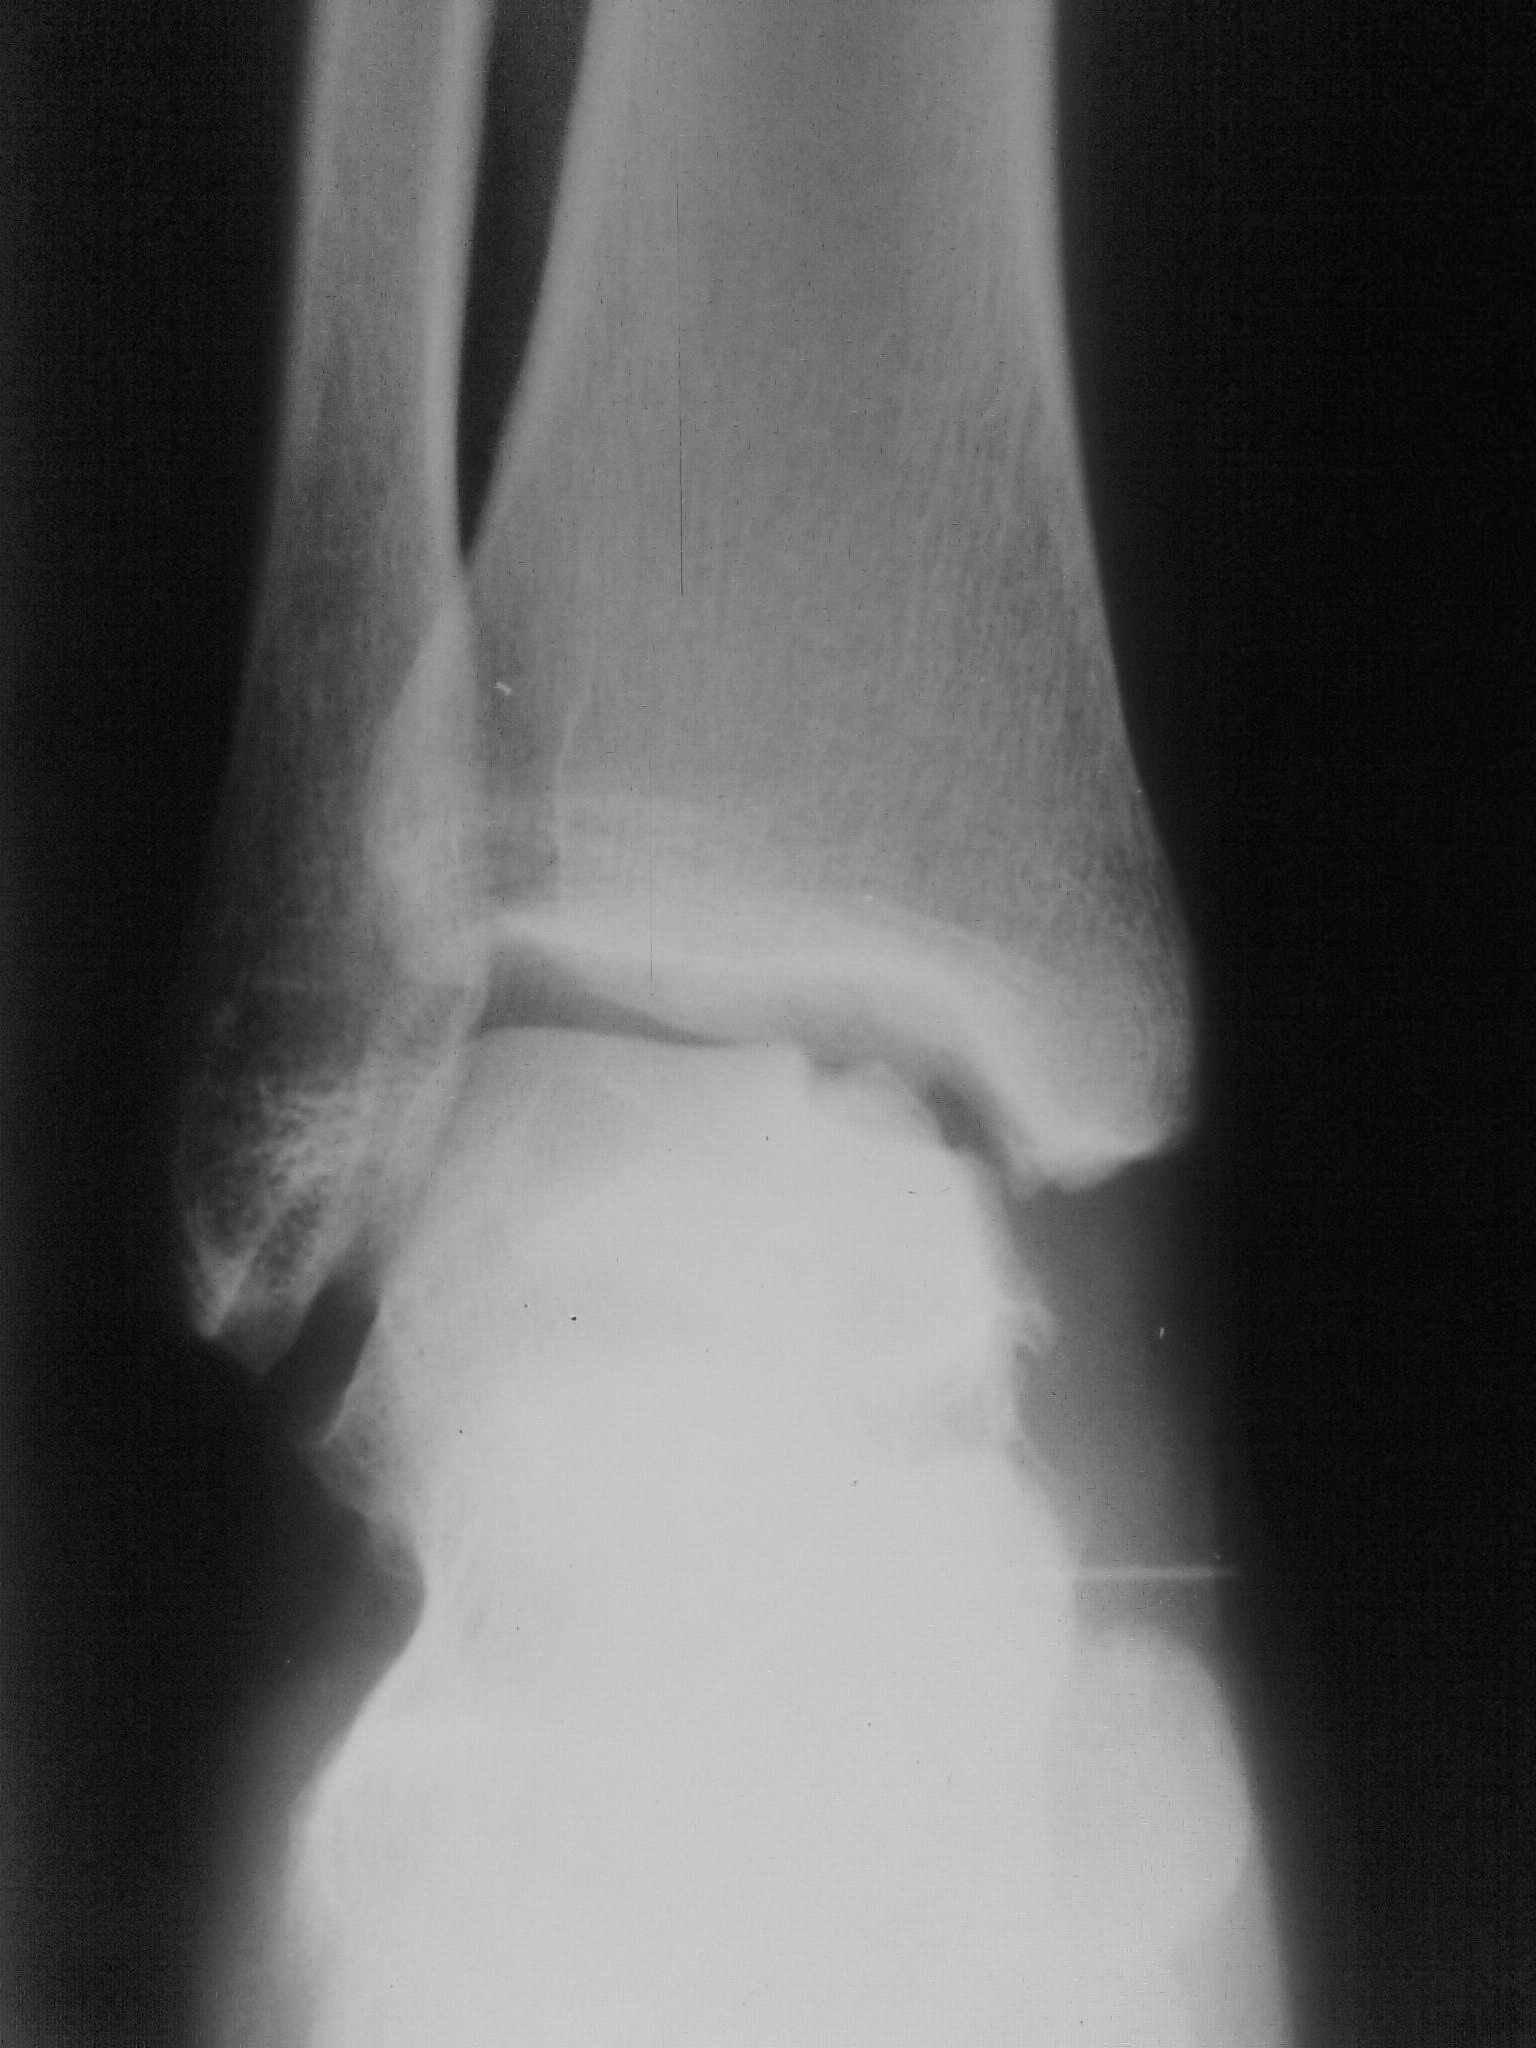

Девушка 20 лет обратилась в травмпункт на периодические боли в левом гсс. факта травмы не было. О чем можно думать? -остеохондропатия, - остеомиелит, - tbc, что-то еще?

В перечне остеохондропатий есть остеохондропатия блока таранной кости ( Вейса (Вайса) (Weiss) - Мюллера (Muller) болезнь ), относится к частичным клиновидным остеохондропатиям (по типу болезни Кенига).

Болезнь Мюллера Вейса это немного другое, поражается ладьевидная кость. Смотрите статью в вложениях. В данном случае я думаю о аваскулярном некрозе, рекоммендовал бы МРТ.

Аваскулярный некроз и остеохондропатия (асептический некроз) - это почти одно и тоже по большому счёту. Кроме того, в данном наблюдении, мы имеем так называемый "законченный случай" и признаки уже развивающегося деформирующего артроза. В данном случаее целесообразнее начинать лечение, ибо артроз, безусловно будет прогрессировать.

Я и имела ввиду асептический некроз. Возможно, в литературе напутано с названиями этой патологии. Еще встречала и такие названия - болезнь Диаза (Diaz), болезнь Диаза-Вейса-Мюллера, асептический некроз таранной кости, рассекающий остеохондроз тела таранной кости, остеохондрит таранной кости.

Названий много , а суть одна. Названия по авторам, по всей видимости - это неверно, хотя в какой-то степени отражают историческое первенство описания (или плагиата) того или иного заболевания.

Я бы не постеснялся трактовать данные случаи как остеохондропатии, по типу б-ни Кенига.

Весьма похоже уважаемая коллега, и очень кажется убедительным, именно в сравнении с болезнью Кенига.

Болезнь Мюллера Вейса это немного другое, поражается ладьевидная кость. Смотрите статью в вложениях.

В данном случае я думаю о аваскулярном некрозе, рекоммендовал бы МРТ.